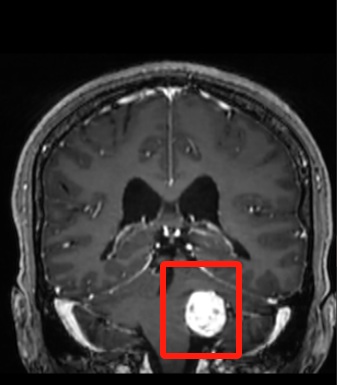

Since the operation of the Sino-German cooperative hospital, the team led by Prof. Madjid Samii has maintained close ties with us and regularly organizes telemedicine consultations with our neurosurgery team. Now, in order to better leverage the advantages of our hospital as an international medical institution, we are inviting foreign experts to the hospital to provide face-to-face services for patients. PART.01 After 3 years of seeking medical treatment, the root cause of hearing loss was finally identified The patient is a middle-aged woman. She began her long journey of seeking medical treatment three years ago after noticing hearing loss in her left ear. It wasn't until December of last year that she came to the Neurosurgery Department of our hospital. Following a series of specialized examinations, including MRI (magnetic resonance imaging), the root cause was finally identified—it turned out to be a left vestibular schwannoma. The area encircled in the red box indicates a left vestibular schwannoma. This type of tumor is a common intracranial one that may be accompanied by symptoms such as tinnitus, hearing loss, and balance disorders. According to the analysis of the imaging data, the patient's tumor has "grown" to approximately 3 centimeters in size. “I’ve heard that Professor BAO Yuhai, a renowned neurosurgery expert from Beijing Xuanwu Hospital, is now practicing at your hospital. Can I ask for his help to operate on me?" After receiving an affirmative response from the physician, the patient felt greatly relieved. PART.02 Two renowned experts collaboratively perform the surgery During the patient’s inpatient stay, Prof. Daniel Hänggi, upon learning about her condition, made the decision to join the neurosurgery team for collaborative treatment. On the morning of April 29th, Prof. Daniel Hänggi and the neurosurgery team conducted a thorough preoperative discussion and planning. With all preparations in place, they performed the surgery in the hospital's Hybrid Operating Room with the intraoperative MRI system. In the field of neurosurgery, performing a surgery tackling vestibular schwannoma is considered to be hellishly difficult. This is because the site where the tumor grows is extremely narrow. Additionally, it is densely packed with numerous tiny nerves and blood vessels. To ensure a successful surgery, the margin of error must be strictly controlled within millimeters. During the surgery, Prof. BAO Yuhai, the chief surgeon, drawing upon his extensive experience from over a thousand surgeries, skillfully navigated around the delicate and fragile nerves and blood vessels. Prof. Daniel Hänggi, standing by his side, provided great support, sharing his advanced experience gained from the International Neuroscience Institute (INI) in Hannover, Germany. With the combined efforts of these two renowned neurosurgery experts, the surgery was remarkably successful. The patient's intracranial tumor was completely removed, with every effort being made to preserve the patient's facial and acoustic nerves. PART.03 Looking to the Future, Exploring Possibilities "In the future, I will continue to provide medical and technological support and work closely with the neurosurgery team to help more Chinese patients in need." said Prof. Daniel Hänggi emotionally, deeply touching the neurosurgery medical staff present. As the only municipal public hospital in China jointly operated by Chinese and foreign partners, our hospital actively opens up more possibilities for patients' health and well-being by integrating diverse international perspectives and cutting-edge medical technologies. This Sino-German cooperative surgery has accumulated valuable experience for us to better serve patients. We will organize more Sino-foreign diagnosis and treatment activities to continuously provide patients with more advanced and higher-quality medical technologies and services.